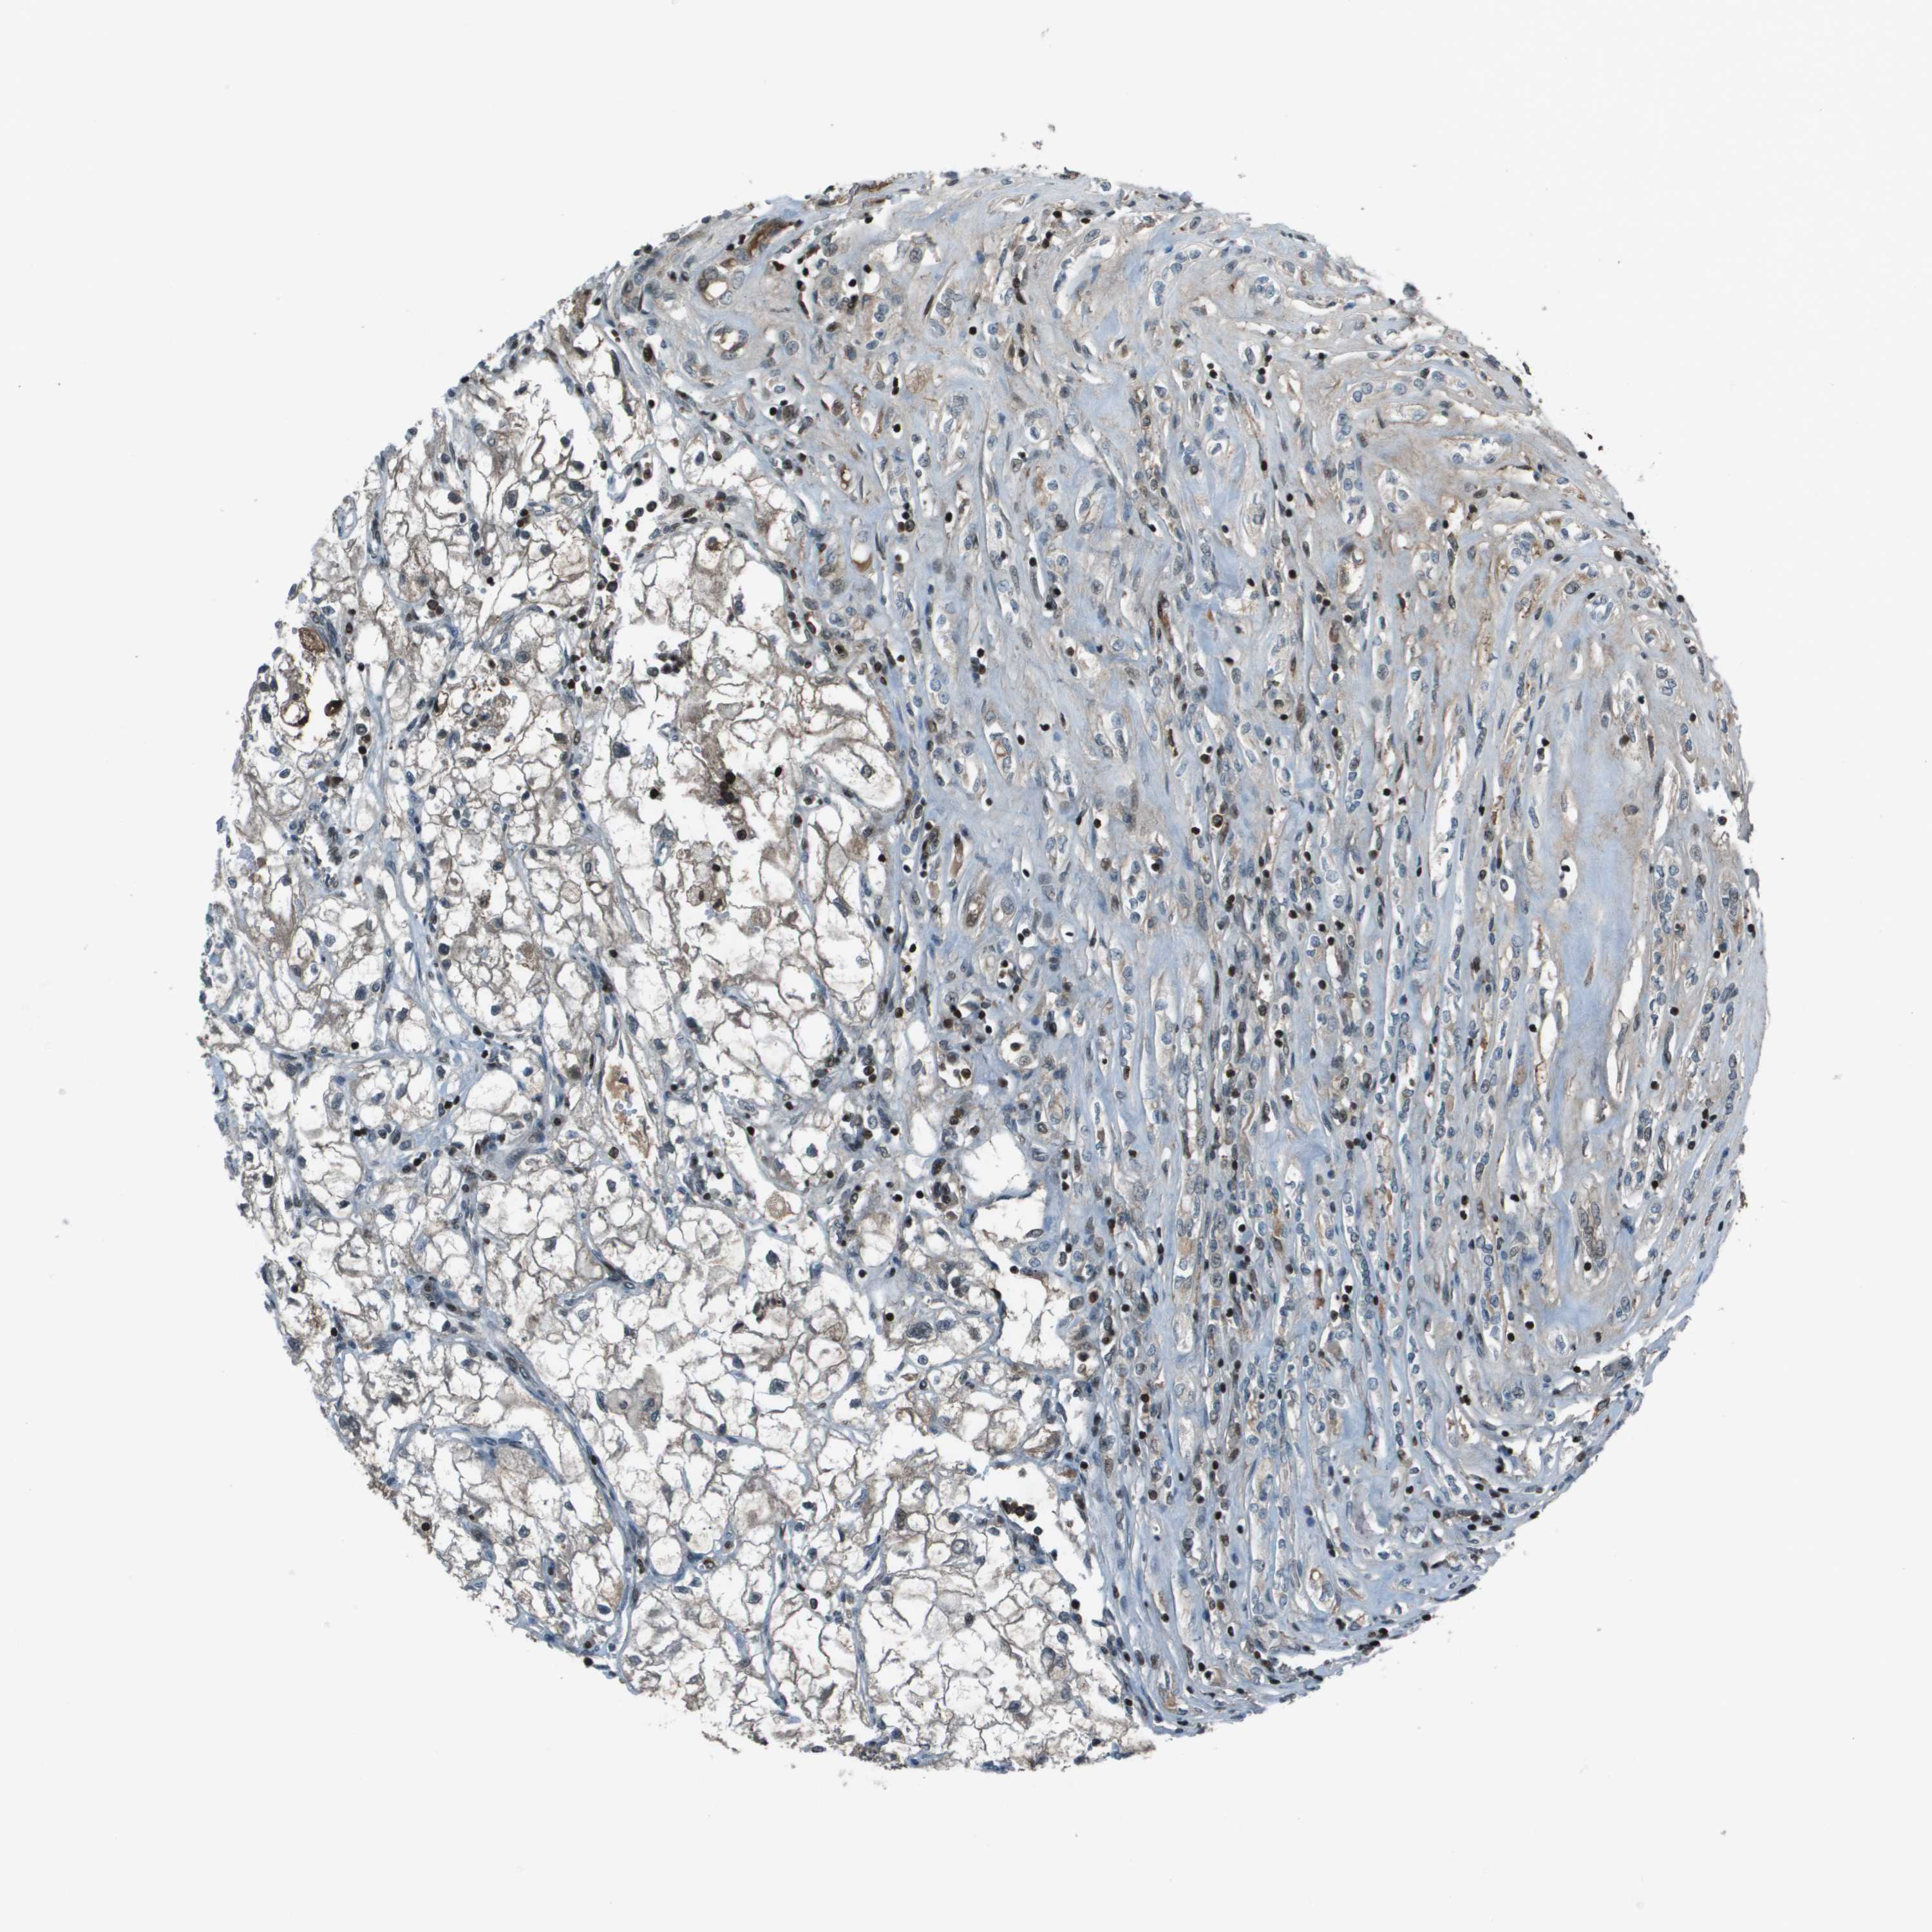

CANCER RENAL CANCER Show tissue menu

KICH TCGA KIRC TCGA KIRC VALIDATION KIRP TCGA PROTEIN RCC CPTAC PROTEIN EXPRESSION